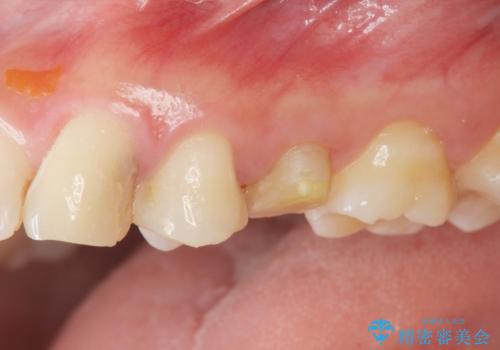

- [ 再生治療・歯周外科・小矯正・セラミック補綴 ] 前歯の歯周病治療- 担当医 大元洋佑 ![[ 再生治療・歯周外科・小矯正・セラミック補綴 ]  前歯の歯周病治療の症例 治療前](https://seimitsushinbi.jp/wp/wp-content/uploads/2022/12/83065c2454a29ed71cf190e15a6106f4-500x350.jpg?v=1671673398) ![[ 再生治療・歯周外科・小矯正・セラミック補綴 ]  前歯の歯周病治療の症例 治療後](https://seimitsushinbi.jp/wp/wp-content/uploads/2022/12/ec16e37ee53325a6f6629b94759f5513-500x350.jpg?v=1671673454)